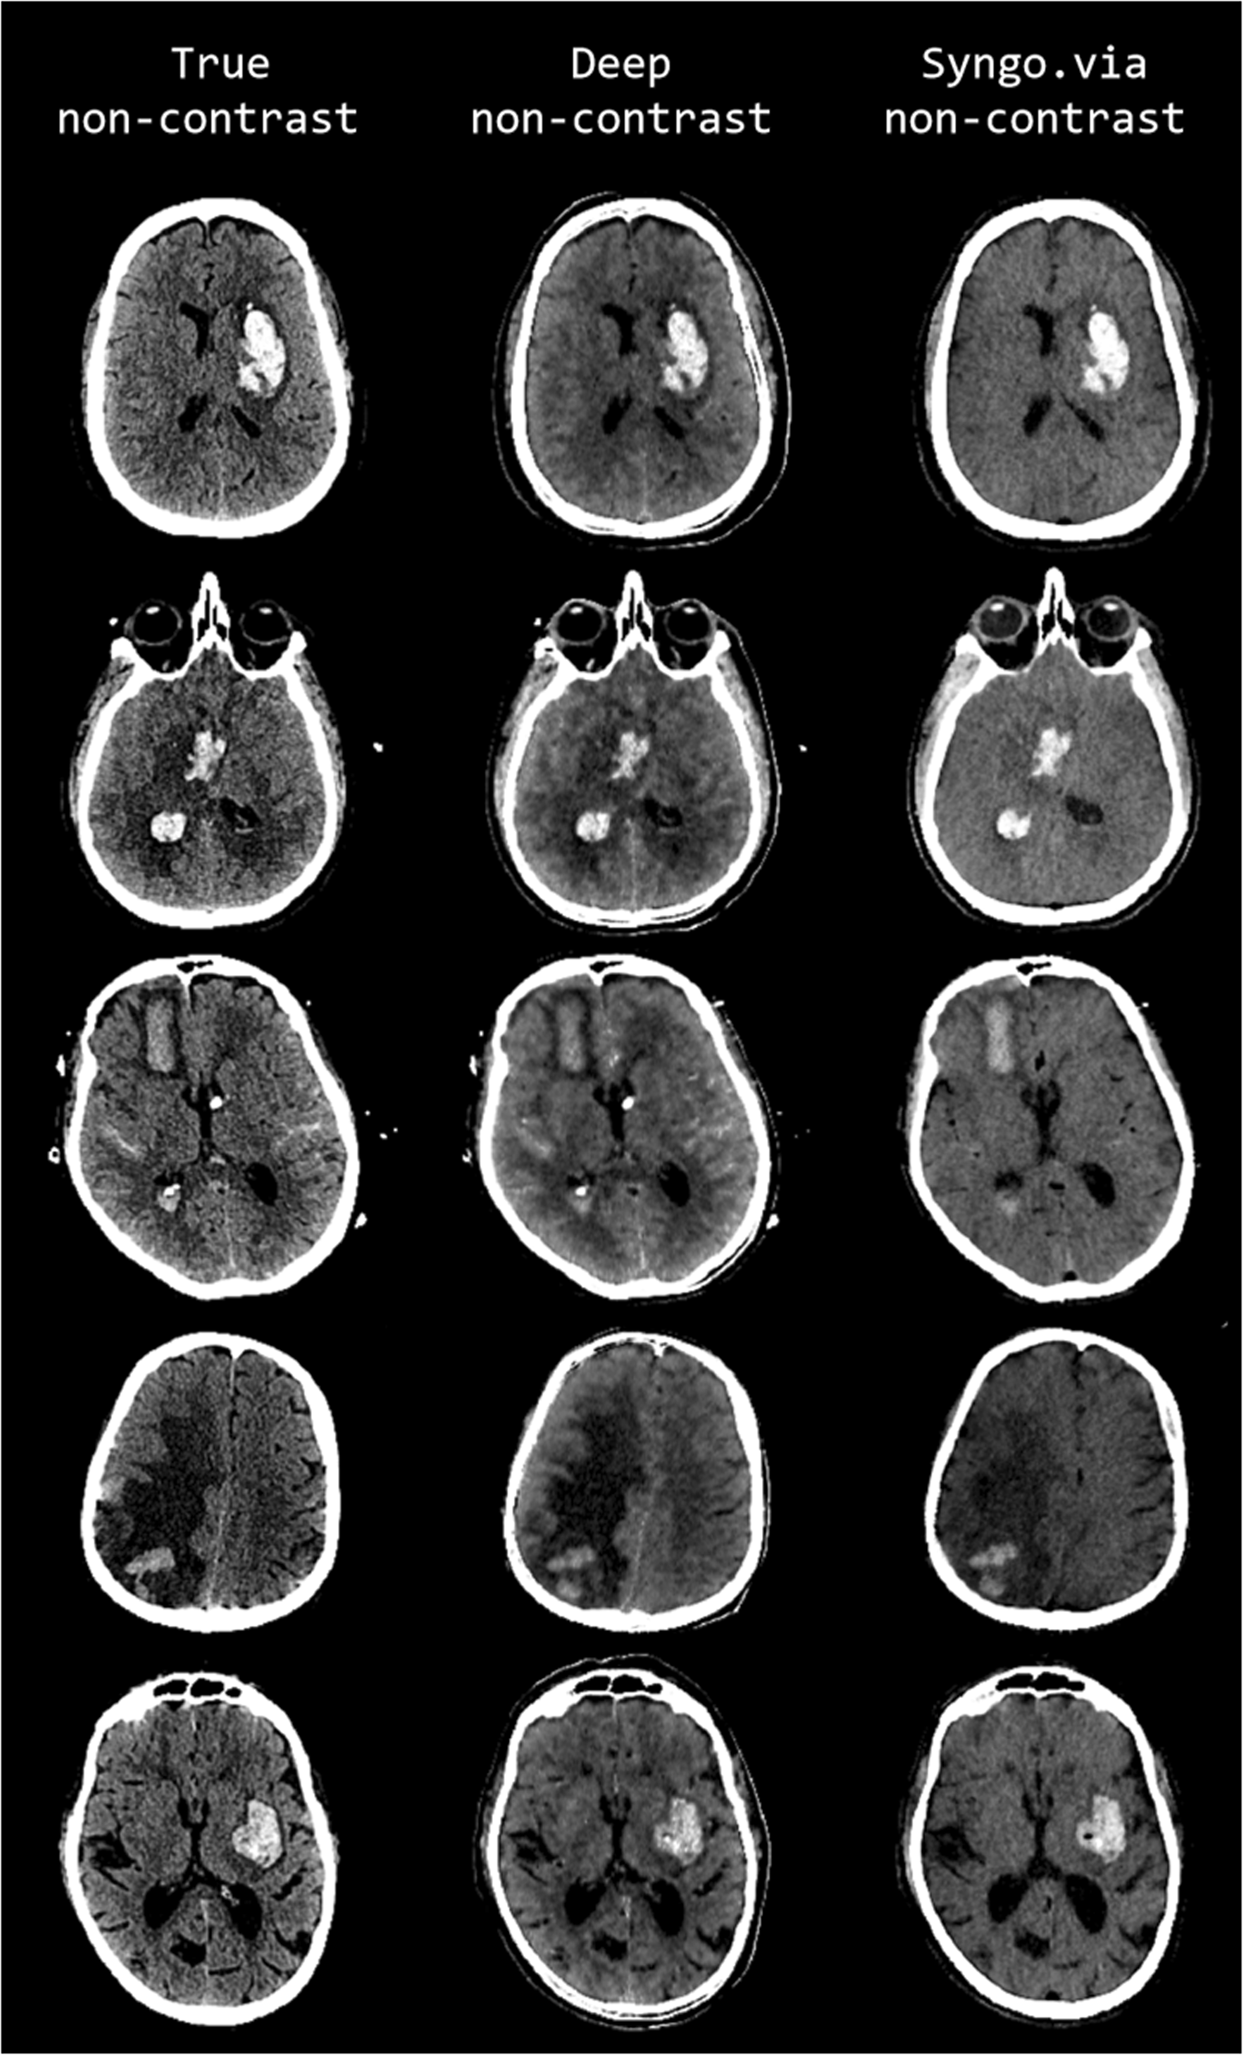

Figure 2

From: Physics-informed Deep Learning for Dual-Energy Computed Tomography Image Processing

Comparison of representative examples of predicted DNC images generated using the proposed CNN (middle column, display window (40, 80)), TNC images (left column (display window (40, 80)), and S-VNC images reconstructed using a conventional material decomposition algorithm (right panel, display window (20, 60)) in the evaluation of hemorrhagic stroke. Reduced SNR on the S-VNC images erroneously de-emphasizes areas of acute hemorrhage. In comparison, the predicted DNC images demonstrate increased conspicuity of normal brain anatomy and various intracranial pathologies, including vasogenic edema, hemorrhagic infarction and subarachnoid hemorrhage. Moreover, the predicted DNC images have less noise than the TNC images, improving the visibility of subtle intracranial hemorrhage. First row: 49-year-old male presenting with unilateral weakness and aphasia secondary to acute ICH within the left basal ganglia. Vasogenic edema surrounding the ICH is more easily identified on the DNC image than the S-VNC image. Second row: 47-year-old unresponsive female with a large acute ICH in the right basal ganglia and intraventricular hemorrhagic extension. There is trans-ependymal CSF flow, consistent with acute hydrocephalus as a result of intraventricular hemorrhagic extension, which is well-visualized on the predicted DNC and TNC images and not well seen on the S-VNC image. Third row: 72-year-old female with acute subarachnoid hemorrhage and acute ICH secondary to a ruptured anterior communicating artery aneurysm. The TNC and predicted DNC images depict multifocal acute subarachnoid hemorrhage and trans-ependymal CSF flow from acute hydrocephalus, which are not identifiable on the S-VNC image. Note that the differentiation and extent of acute subarachnoid hemorrhage is improved on the predicted DNC image compared to the TNC image, most notable along the anterior left frontal lobe. Fourth row: 64-year-old male presenting with altered mental status secondary to a large right parietal ICH, which is better evaluated in extent on the predicted DNC image compared to the S-VNC image. The extent of surrounding vasogenic edema is also better characterized on TNC and predicted DNC images. Slight posterior morphological differences between the TNC and other images are secondary to registration inaccuracy. Fifth row: 80-year-old male presenting with acute-onset right facial droop, right-sided weakness and expressive aphasia secondary to an acute ICH involving the left basal ganglia and left insula. Both TNC and predicted DNC images better delineate normal anatomy and the extent of vasogenic edema surrounding the ICH. Moreover, the predicted DNC image demonstrates reduced noise in comparison to the TNC image, allowing for better gray-white matter differentiation.